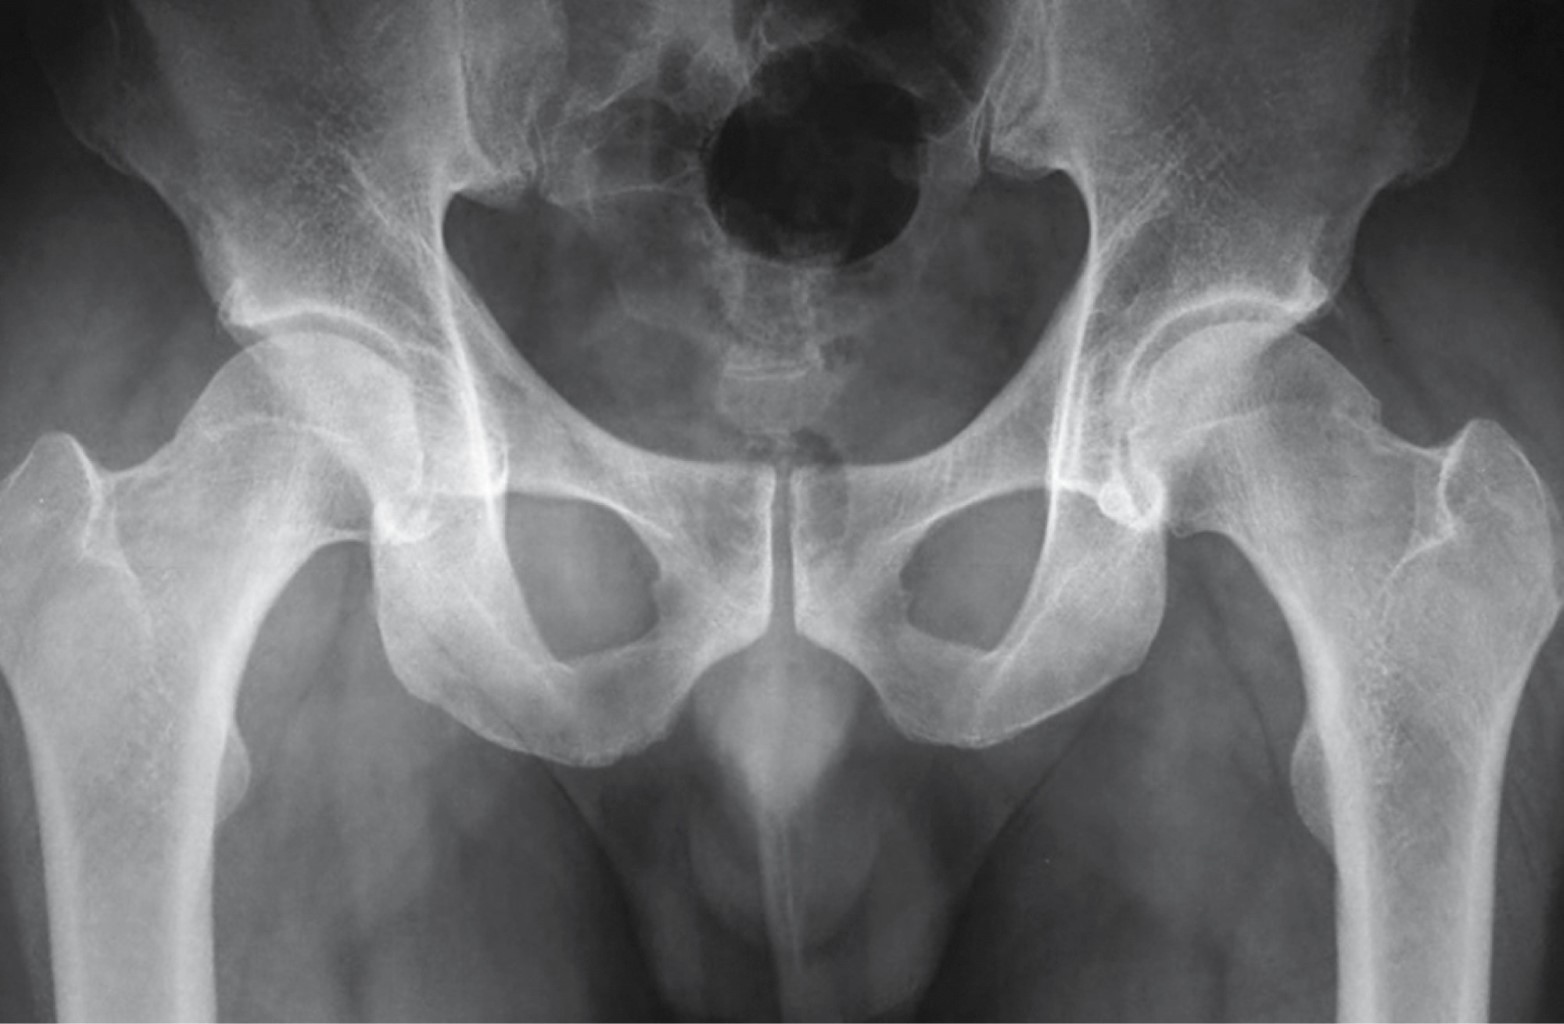

Masculino de 36 años de edad, profesionista, sin antecedentes de importancia, con dolor inguinal de un año de evolución, que se exacerba posterior a juego de balompié, obligándolo a suspender la actividad. A la exploración dirigida, postura y marcha sin alteraciones, dolor a la exploración de articulación coxofemoral durante la rotación interna y aducción con flexión de cadera a 90o, al igual que durante abducción con cadera en posición neutra. En radiografía anteroposterior de cadera se observa anormalidad de fémur izquierdo en la unión cabeza cuello, correspondiendo a pinzamiento femoroacetabular tipo leva (Figuras 1, 2 y 3).

El pinzamiento femoroacetabular tipo leva (FAI tipo CAM por sus siglas en inglés) (la leva es un elemento mecánico que está sujeto a un eje en un punto que es excéntrico a su centro geométrico) es una causa conocida de dolor inguinal que puede provocar osteoartritis de la cadera. Los pacientes que padecen esta afección son principalmente jóvenes que experimentan dolor inguinal durante los movimientos de rotación interna y aducción con la articulación coxofemoral en flexión de 90o; ocasionado por contacto anormal entre la unión cabeza-cuello femoral y el borde acetabular debido a anormalidad anatómica del fémur, ya que la morfología de la cabeza femoral no es esférica por alteración o anomalía del cuello femoral.1 Esta anormalidad se observa en 40% de los pacientes que desarrollan osteoartritis de cadera; puede ser secundaria a enfermedades del fémur proximal típicas de la infancia, incluidas secuelas de epifisiolistesis de la cabeza femoral, enfermedad de Legg-Calvé-Perthes, a infección de la articulación coxofemoral en la infancia y traumatismos de la articulación. Al ser una patología dinámica su desarrollo también está relacionado con actividad deportiva intensa. La prevalencia de la deformidad del choque femoroacetabular tipo leva es mayor en el género masculino.2 Su diagnóstico temprano resulta importante para establecer estrategias de tratamiento en pacientes con dolor de cadera preartrítico, la serie radiográfica de cadera al igual que la resonancia magnética y la tomografía con medición del ángulo alfa proporcionan las pautas de medición prequirúrgica.3 El pinzamiento femoroacetabular se puede tratar mediante procedimiento quirúrgico abierto o por artroscopia. Se informan complicaciones clínicamente relevantes en 4.8% de los pacientes con cirugía abierta y la tasa general de complicaciones asociadas con la artroscopia de cadera es discretamente menor (4%).4

Figura 2